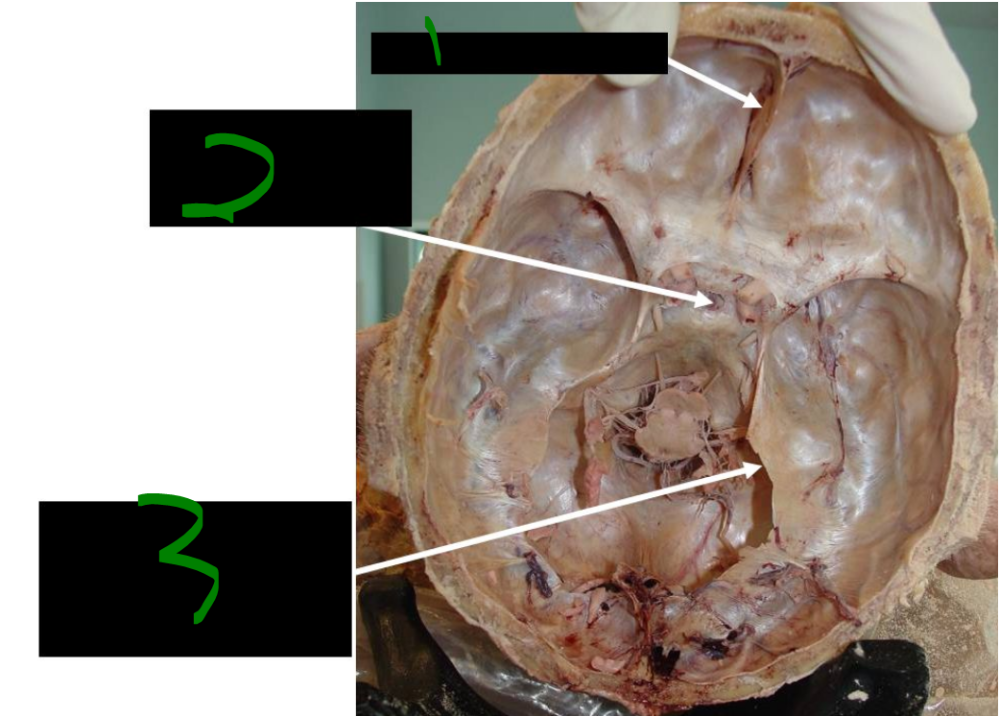

The precentral gyrus, where the primary motor cortex resides, is organized ______, meaning specific regions control specific ______ parts.

somatotopically, body

54